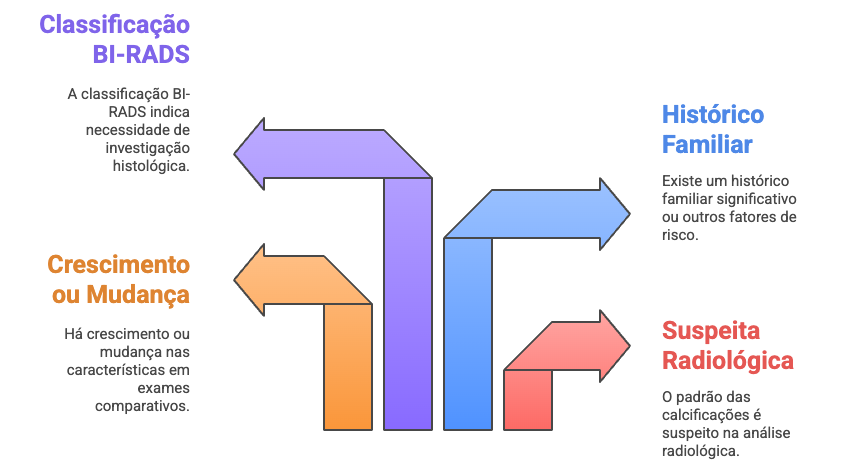

A palavra “biópsia” pode assustar, mas é um procedimento fundamental para esclarecer dúvidas. A biópsia não é necessária para todas as calcificações, apenas em situações especificas, como:

- O padrão das calcificações desperta suspeita na análise radiológica

- Observo crescimento ou mudança nas características em exames comparativos

- Existe histórico familiar significativo ou outros fatores de risco

- A classificação BI-RADS indica necessidade de investigação histológica